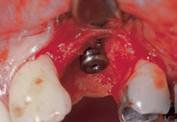

Dieser Patient wurde bereits im Jahr 1991 behandelt. Der Fall zeigt eine der ersten klinischen Anwendungen von Geistlich Bio-Oss Collagen. Aufgrund des intraalveolären Knochendefekts wurde eine Frühimplantation mit gleichzeitiger Augmentation durchgeführt. Die Implantation wurde 6 Wochen nach Extraktion des Prämolars vorgenommen. In der postoperativen Phase erfolgte eine unauffällige Weichgewebeheilung nach Extraktion. Für die Implantatinsertion wurde der Frühimplantationsansatz mit einer Heilungsphase von 6 Wochen gewählt. Die Knochenaugmentation wurde gleichzeitig mit der Implantatinsertion durchgeführt. Das Implantat wurde nach der Lappenpräparation an einer Stelle mit einem schweren Knochendefekt eingesetzt.

Für den Knochenaufbau wurde Geistlich Bio-Oss Collagen in den Defekt appliziert und nach der Augmentation die Eingriffsstelle mit einem Kollagenvlies abgedeckt. Weitere 6 Monate nach dem Eingriff wurde die endgültige Kronenrestauration eingesetzt. Bei der weiteren Nachuntersuchung nach nunmehr 25 Jahren zeigte die Röntgenaufnahme ein stabiles Implantatlager und das klinische Bild bei der Nachkontrolle einen ästhetischen Zahnstatus.